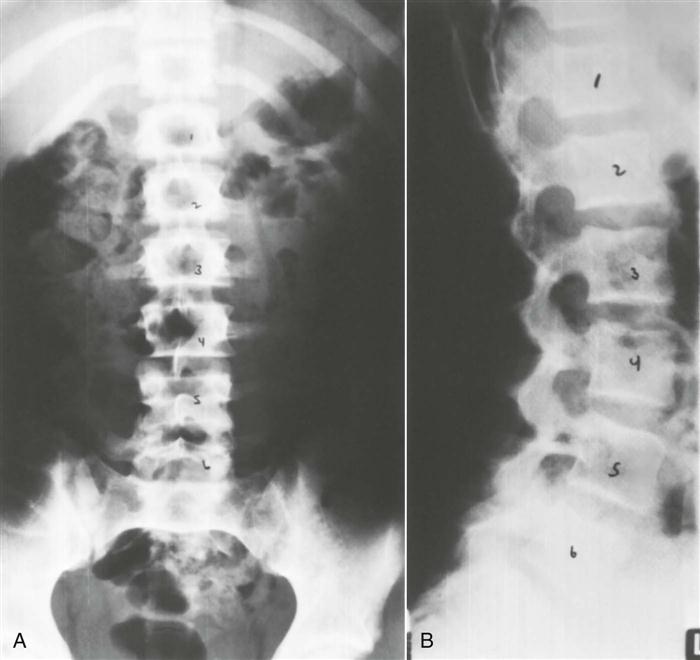

Normally, anteroposterior and lateral views are taken.258 In some cases, two lateral views may be taken, one that shows the whole lumbar spine, and one that focuses on the lower two segments. Oblique views are taken if spondylolysis or spondylolisthesis is suspected.123

With this view (Figure 9-96), the examiner should note the following:

With this view (Figure 9-106), the examiner should note the following: